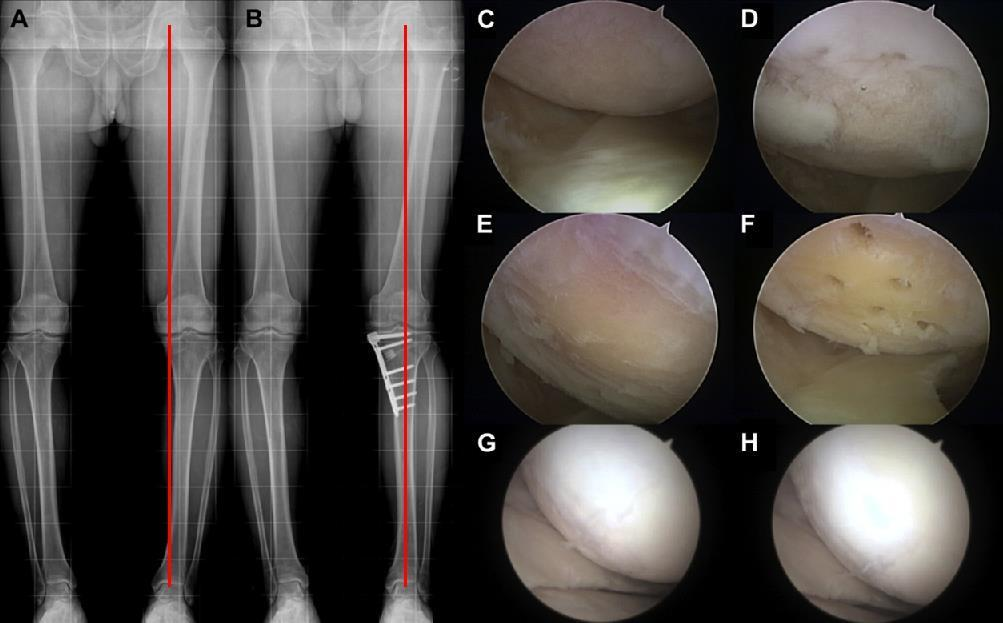

据了解,保膝治疗的两种主要手术方式是截骨术和单髁置换术,可以精准解决患者膝关节疼痛的病因,处理膝关节病变,最大限度保留患者膝关节原有功能。其中,截骨术是通过纠正下肢异常力线,改变膝关节异常应力集中,在解决患者疼痛症状的同时,进一步阻止异常应力对膝关节的进一步损伤,膝关节内部所有的软骨韧带半月板都得到了保留,患者恢复健康后,拥有完全正常的膝关节功能。内侧单髁置换术,精准置换患者膝关节内侧间室磨损,而膝关节外侧健康的软骨和半月板得到了保留,膝关节的内外侧副韧带、前后交叉韧带都维持原有的状态,为患者保留原有的膝关节运动功能。

图片

截骨矫形示意图

截骨矫形术后磨损的软骨再生